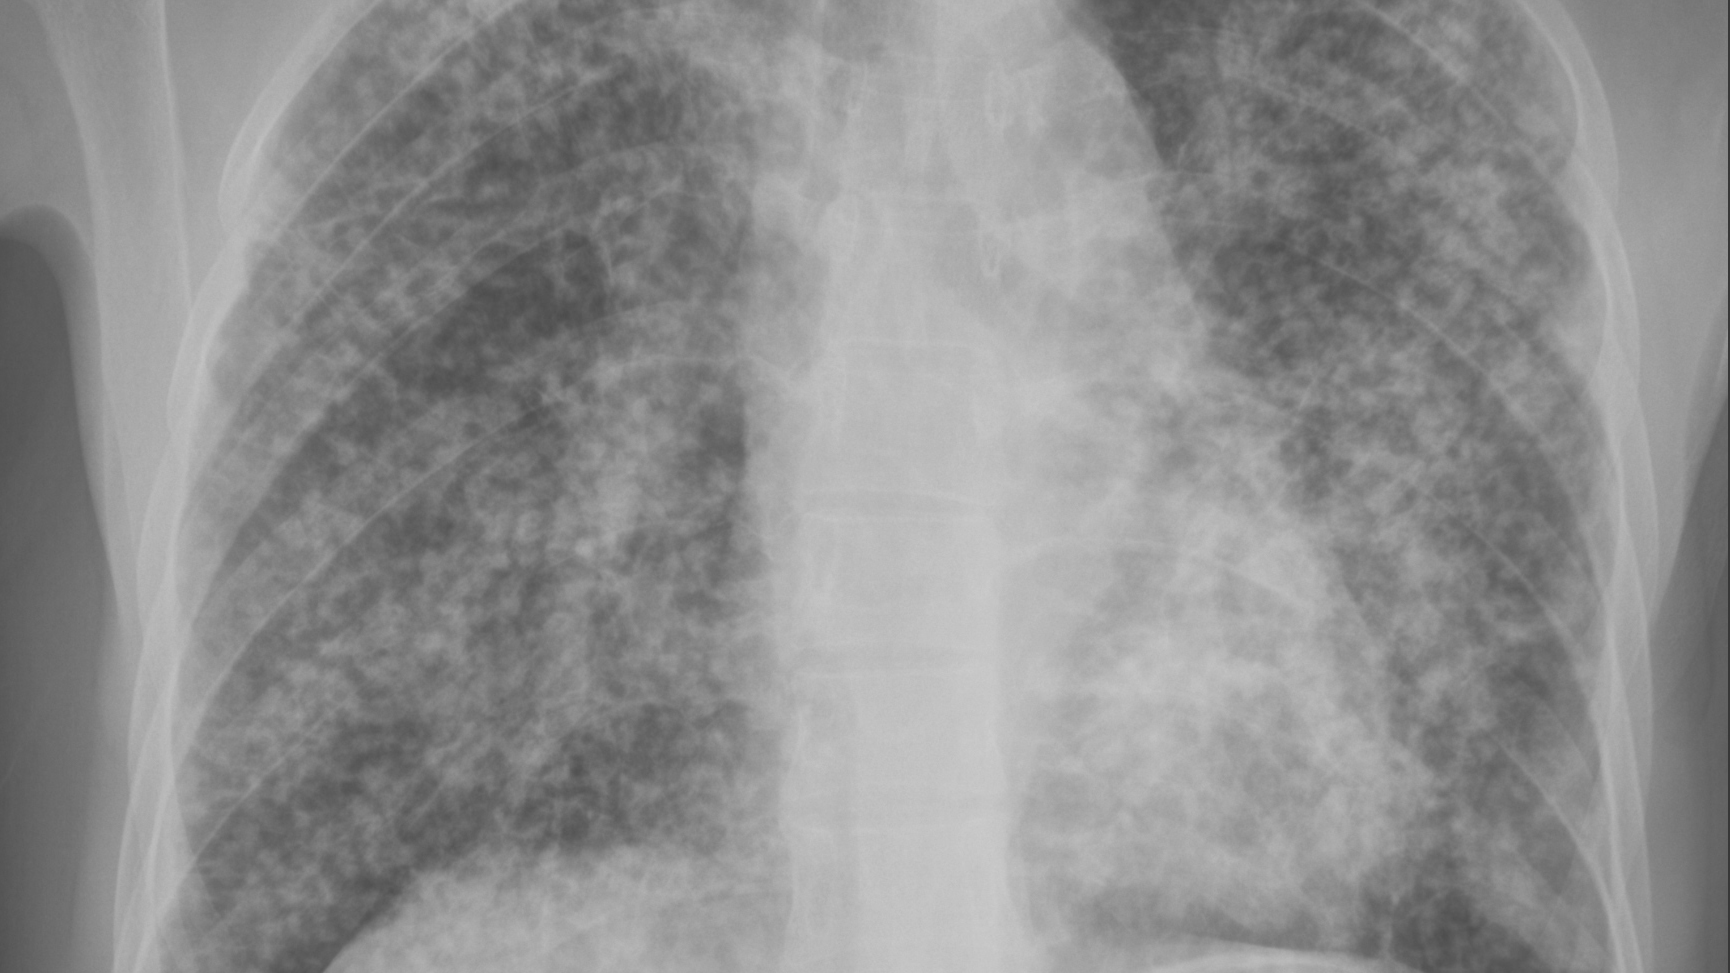

胸部影像学检查:ILO分类的"读片密码"

ILOInternational Labour Organization,国际劳工组织)尘肺病影像学分类:

基于胸部X光片或高分辨率CTHRCT

1. 小阴影(Small Opacities):

尘肺病的早期表现

粉尘沉积引起的小结节、网状影

密度(Profusion):

评估小阴影的数量/密集程度

分为4个大类、12个小类:

0/-:无尘肺

0/0:无尘肺

0/1:可疑尘肺

1/01/11/2期尘肺

2/12/22/3期尘肺

3/23/33/+期尘肺

分期意义:

期:小阴影少量,肺功能可能正常或轻度下降

期:小阴影中等量,肺功能中度下降

期:小阴影大量,肺功能重度下降

形状和大小:

圆形:p(直径<1.5 mm)、q1.5-3 mm)、r3-10 mm

不规则形:stu

矽肺多为圆形

石棉肺多为不规则形

分布:

上、中、下肺区

2. 大阴影(Large Opacities):

尘肺病晚期表现

大块纤维化(Progressive Massive Fibrosis, PMF

分类:

A类:单个大阴影长径1-5 cm,或多个大阴影总和<5 cm

B类:单个或多个大阴影,总面积不超过右上肺区面积

C类:大阴影总面积>右上肺区面积

意义:

大阴影出现病情重、预后差

常伴严重呼吸功能障碍